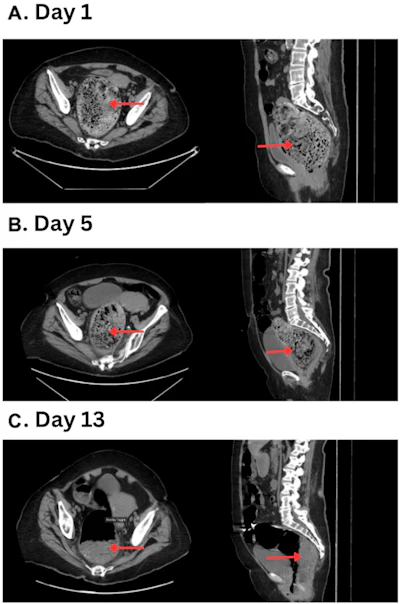

- CT reveals new use for Coca-Cola: Dissolving fecalomasby Kate Madden Yee on April 22, 2026 at 5:13 pm

CT imaging helped diagnose a large fecaloma and track a patient's response to a Coca-Cola enema to dissolve it.